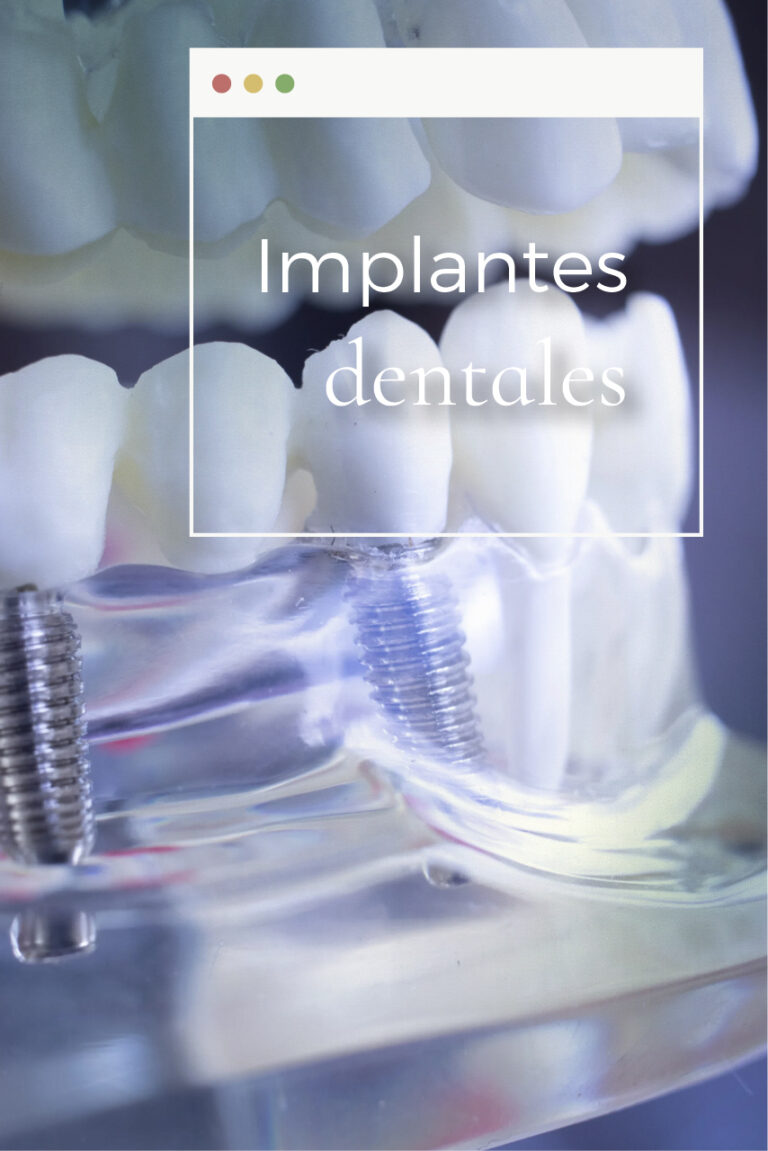

¿Qué son los implantes dentales?

Los implantes dentales son estructuras de titanio biocompatible que se colocan en el hueso maxilar o mandibular para sustituir la raíz de un diente perdido.

Tras un proceso llamado osteointegración, el implante se integra en el hueso y permite colocar una corona fija que imita la forma y función de un diente natural.